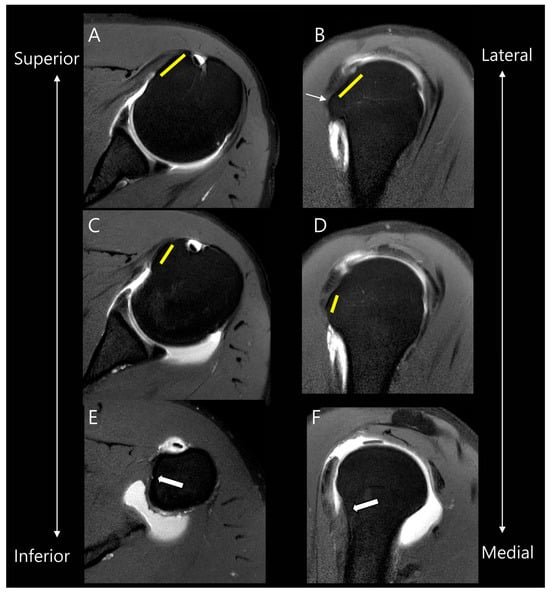

Figure 2.

Anatomy of facets of the subscapularis tendon on MR images. On oblique axial and oblique sagittal MR images, the first facet (yellow lines in (A,B)) is located more superiorly and laterally compared to the second facet (yellow lines in (C,D)). They are separated by a bony ridge (thin arrow in (B)). The following third and fourth facets represent the large muscular insertion in the inferior attachment (thick arrows in (E,F)).